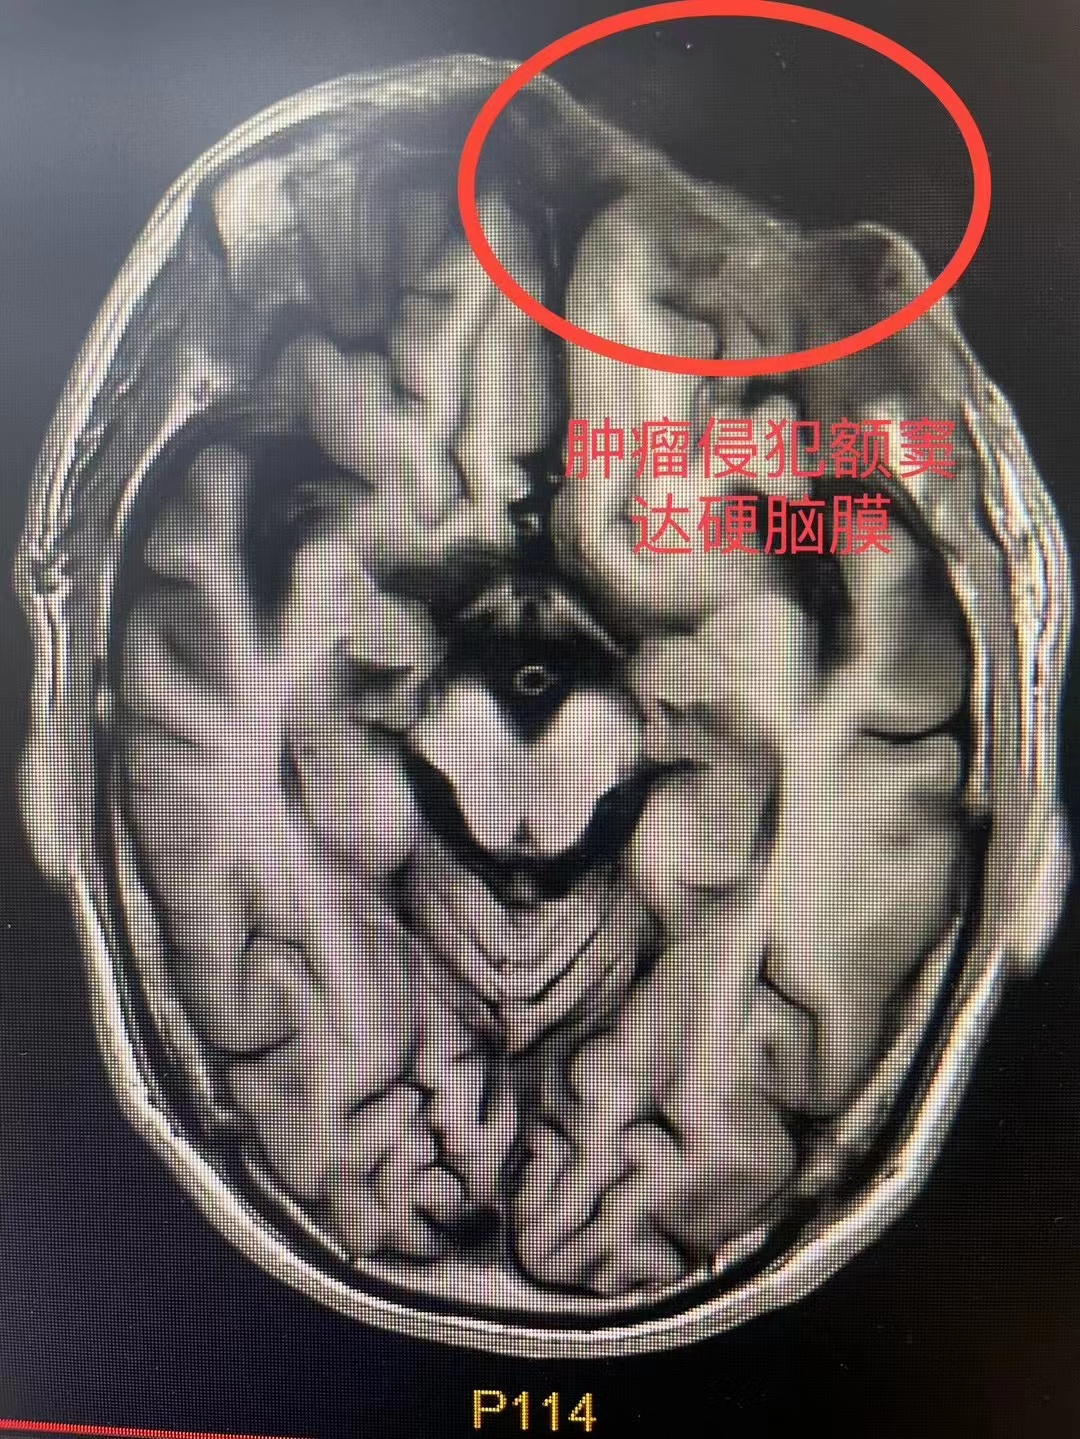

术前CT、MRI所示肿瘤

患者家属曾因陈伯年龄较大犹豫是否进行手术治疗,但手术为该类疾病的首选方案,为了尽量减轻陈伯及家属的顾虑,吕忠耐心详细地给他们讲解了手术的利与弊,最终患者及家属选择手术治疗。为了解决完整切除陈伯眼眶、前颅底、筛窦区肿瘤及封闭修复前颅底、筛窦、眼眶的问题,吕忠联合眼科、综合外科针对陈叔的病情及术前CT、MRI、喉镜等影像资料,对手术方案进行反复讨论和研究,最终选择眼眶基底细胞癌扩大切除(包括前颅底、眼眶、筛窦病灶)+游离股前外皮瓣转移修复。考虑到患者年龄较大,为了缩短手术时间降低手术麻醉风险,最终一边由吕忠团队负责切肿瘤,另一边由综合外科易广田主任团队同时制备股前外游离皮瓣,再由吕忠团队使用皮瓣修复切除肿瘤后的前颅底、鼻窦、眼眶区域皮肤软组织的缺损。经过充分的术前准备,专家团队如期为陈叔进行手术。凭借精湛而熟练的手术技巧及默契的团队配合,历经约3小时,手术顺利结束。术后在科室全体医护人员的精心护理下,陈伯恢复良好。